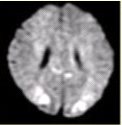

患者女,75岁,突发偏瘫、头痛、头晕10h。既往有高血脂、糖尿病史。MRI表现如下图。

108、单项选择题

初步诊断为()